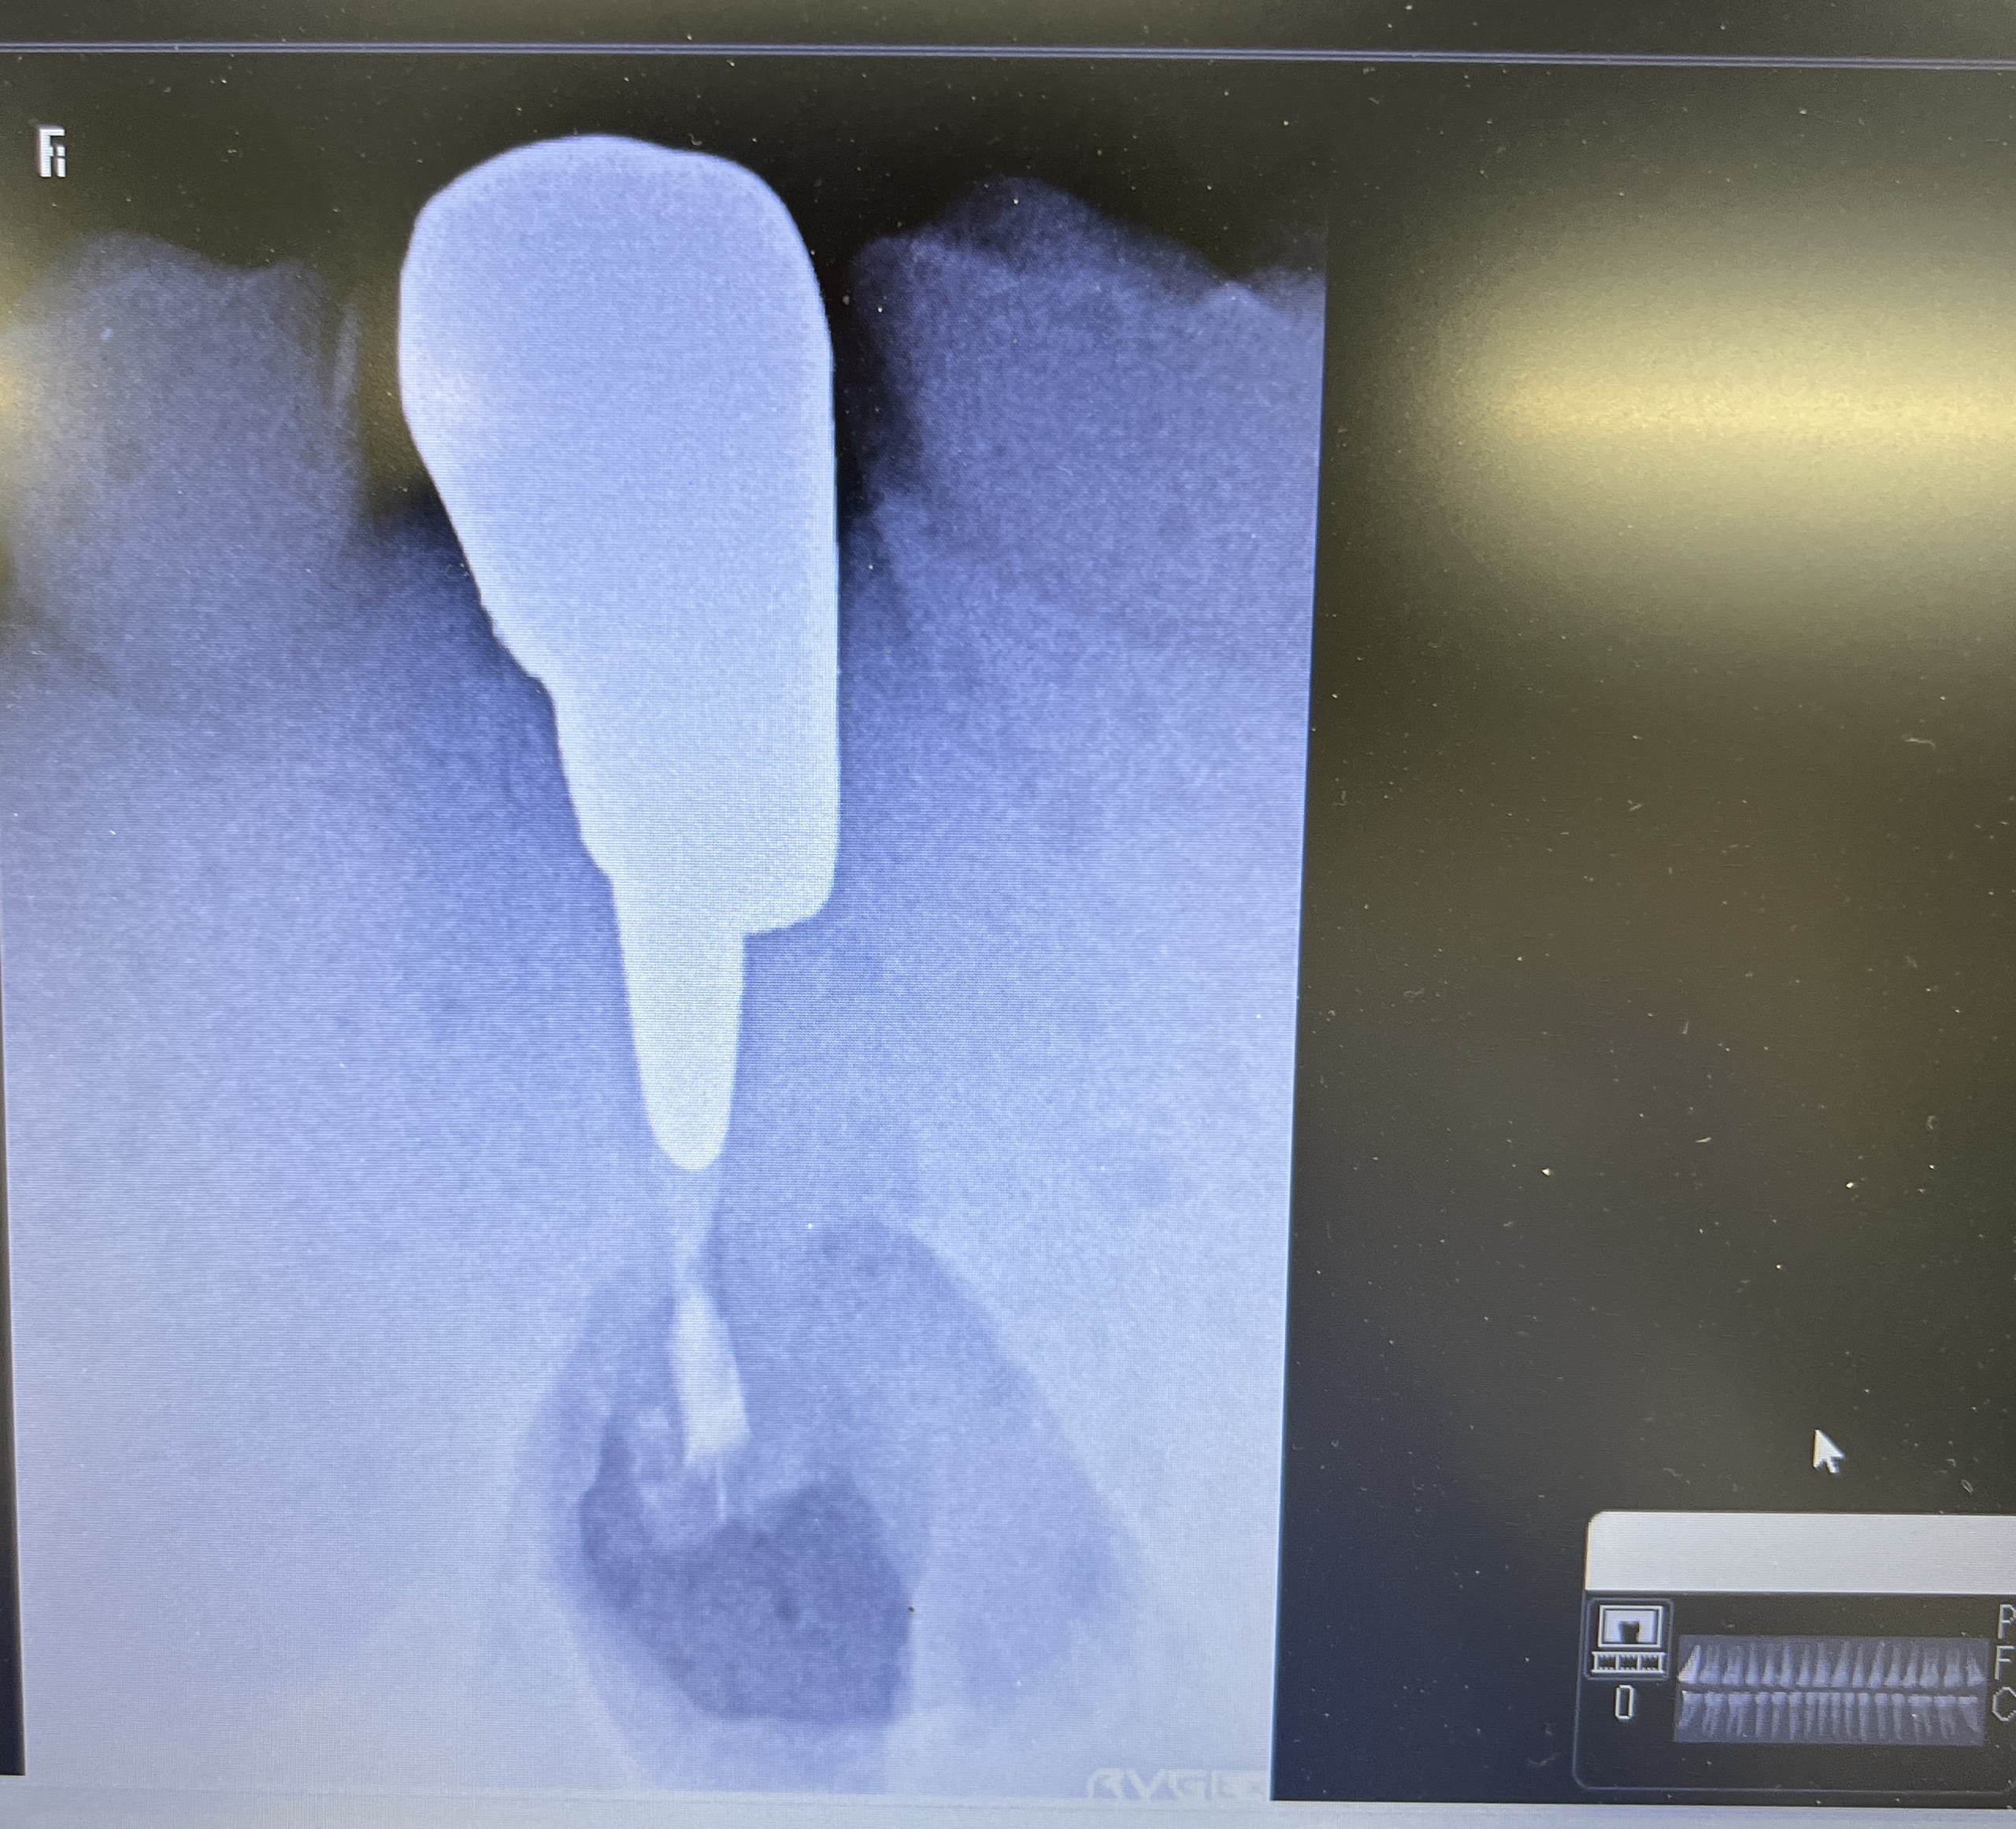

ここで、撮影をしてもらったCBCTを公開しよう。以下である。

これは私なら、もっと切断してやり直すだろう。

絵が、しょっぱいからだ。